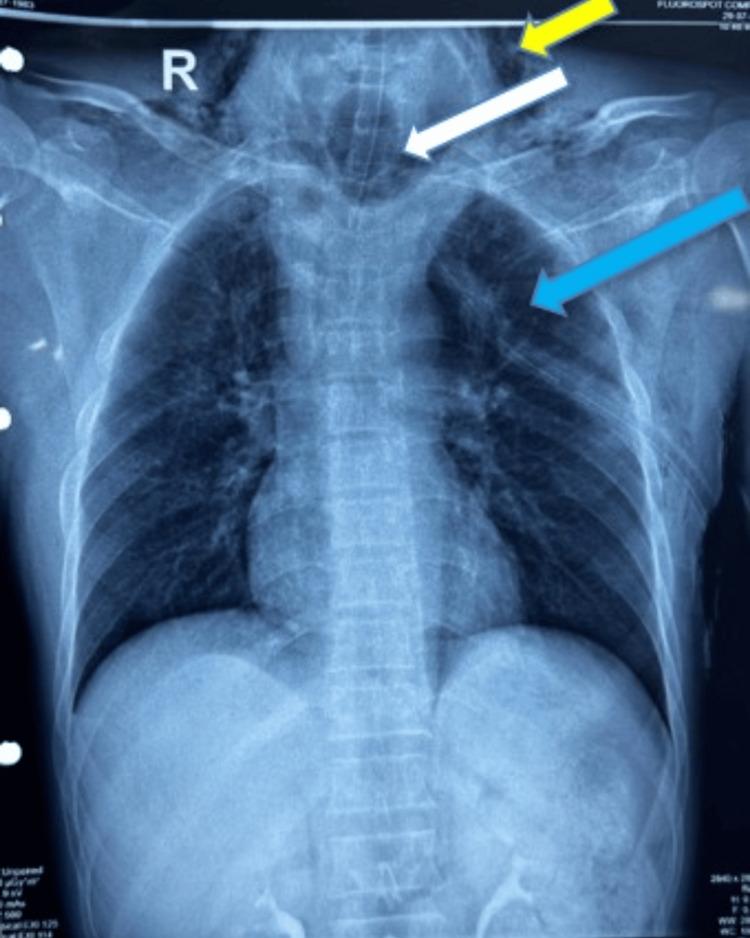

Complete cricotracheal separation is a rare and severe form of laryngeal trauma that most clinicians encounter infrequently, resulting in limited experience with its management. This report discusses the intricate management of a patient with complete cricotracheal separation following a traumatic incident. We present this case to highlight the challenges in the diagnosis and airway management of complete cricotracheal separation. The patient was transferred to our level 1 trauma center with a secured airway via an endotracheal tube from the referring hospital, where they experienced respiratory distress during an extubation attempt before transfer. Respiratory distress may be due to an air leak in the trachea upon deflation of the endotracheal tube cuff. Upon admission, the patient exhibited stable respiratory function, and there were no overt signs of laryngeal injury aside from subcutaneous emphysema around the neck. Imaging via a computed tomography scan revealed a distorted cricotracheal framework, raising suspicion of a high-grade airway injury and prompting surgical exploration. Upon surgical exploration of the neck, a complete cricotracheal transection was discovered with a wide separation of the tracheal ends and an inflated endotracheal tube cuff, which surprisingly prevented any air leak. Intraoperative management included performing a tracheostomy distal to the injury site, followed by a primary end-to-end anastomosis of the cricotracheal injury. This case underscores the crucial importance of prompt and efficient airway management in patients with complete cricotracheal separation. This case underscores the critical need for high clinical suspicion in subtle presentations, the importance of early surgical intervention, and the role of airway devices in stabilizing severe laryngeal trauma.